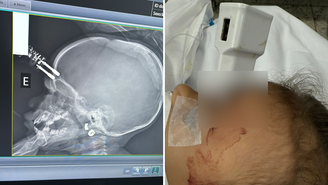

Objeto perfurante atravessou o osso do crânio da criança e atingiu o tecido cerebral

Uma menina de 1 ano e seis meses passou por uma cirurgia de urgência após cair da cama e ter um carregador de celular cravado na testa, em Divinópolis, cidade que fica na região Oeste de Minas Gerais. O acidente aconteceu na última segunda-feira, 12, segundo o médico responsável pelo atendimento, o neurocirurgião Bruno Castro.

Ao Terra, o médico contou que a  principal hipótese é que a menina estava com o carregador na mão quando caiu da cama e o objeto atingiu a cabeça de forma que perfurou a região frontal do crânio, perto do olho.

“Ela realizou uma tomografia de crânio, nós percebemos pela tomografia que esse pino tinha transfixado a calota craniana. Foi realizada uma cirurgia rápida, tranquila, sem intercorrências”, acrescentou o neurocirurgião Bruno Castro.

Foto do cránio da criança pós-cirurgia no Hospital São João de Deus